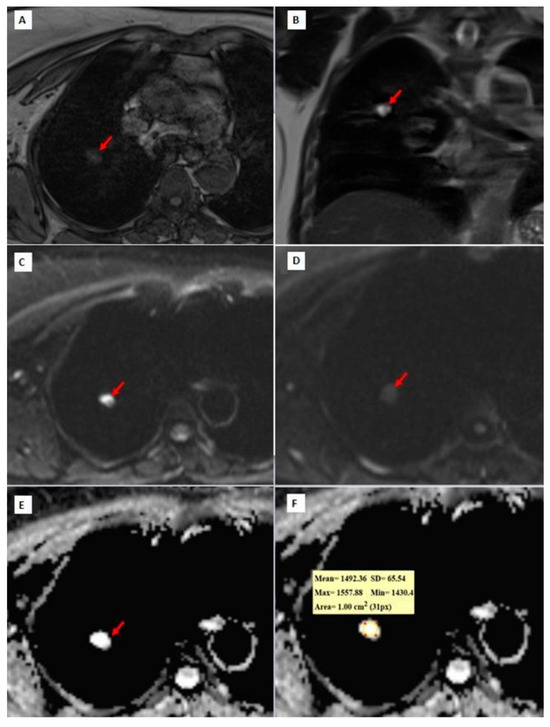

Figure 3, Figure 4 and Figure 5 show thorax MRI images of patients with tumors in the grade 1, 2, and 3 categories, respectively.

Figure 3. A 72-year-old patient diagnosed with grade 1 adenocarcinoma. (A) An axial T1W image showing a hypo-isointense nodule with lobulated contour at the right upper lobe (red arrow). (B) A coronal T2W MRI image showing a hyperintense right upper lobe lung nodule (red arrow); (C,D) b = 0 and b = 800 DW images are shown, respectively. In the b = 0 DW image, there is a hyperintense nodule in the upper lobe of the right lung. In the b = 800 DW images, it is seen that the nodule has lost its signal significantly. (E,F) In the ADC map, the mean ADC value is measured as 1492.36 × 10−6 mm2/s within the lesion.